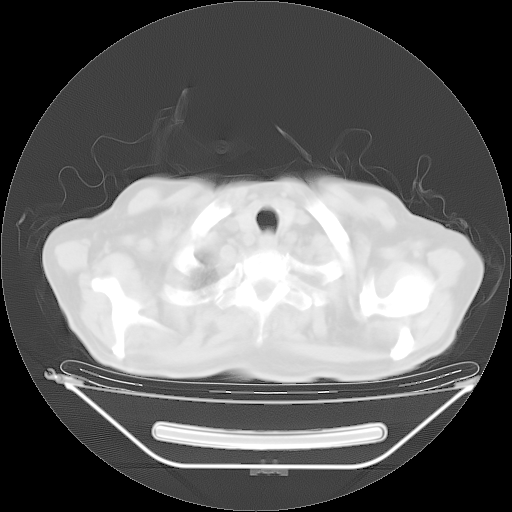

今天复查肺部CT,发现双肺广泛磨玻璃样改变。所以我把3月19日和5月9日相隔50天的肺部CT上传。请大家会诊。

5月9日肺部CT(在4月27日齐鲁医院肺部CT描述部分肺组织磨玻璃样改变,12天后肺组织广泛磨玻璃样改变)

大致读了系列胸部CT:纵隔窗无明显异常,肺窗:从4、27至今:主要是双肺中下野外带可见毛玻璃样改变,目前处于急性肺泡炎阶段,至于原因考虑1、结替组织或胶原血管性疾病所致?2、恶性疾病如恶组在肺部所致的表现或细支气管肺泡癌?3、药物或其它原因如肺蛋白沉着症所致肺泡炎目前不太可能?总之,明天就去请我院的呼吸科、感染科、血液科和临免专家会诊哈。